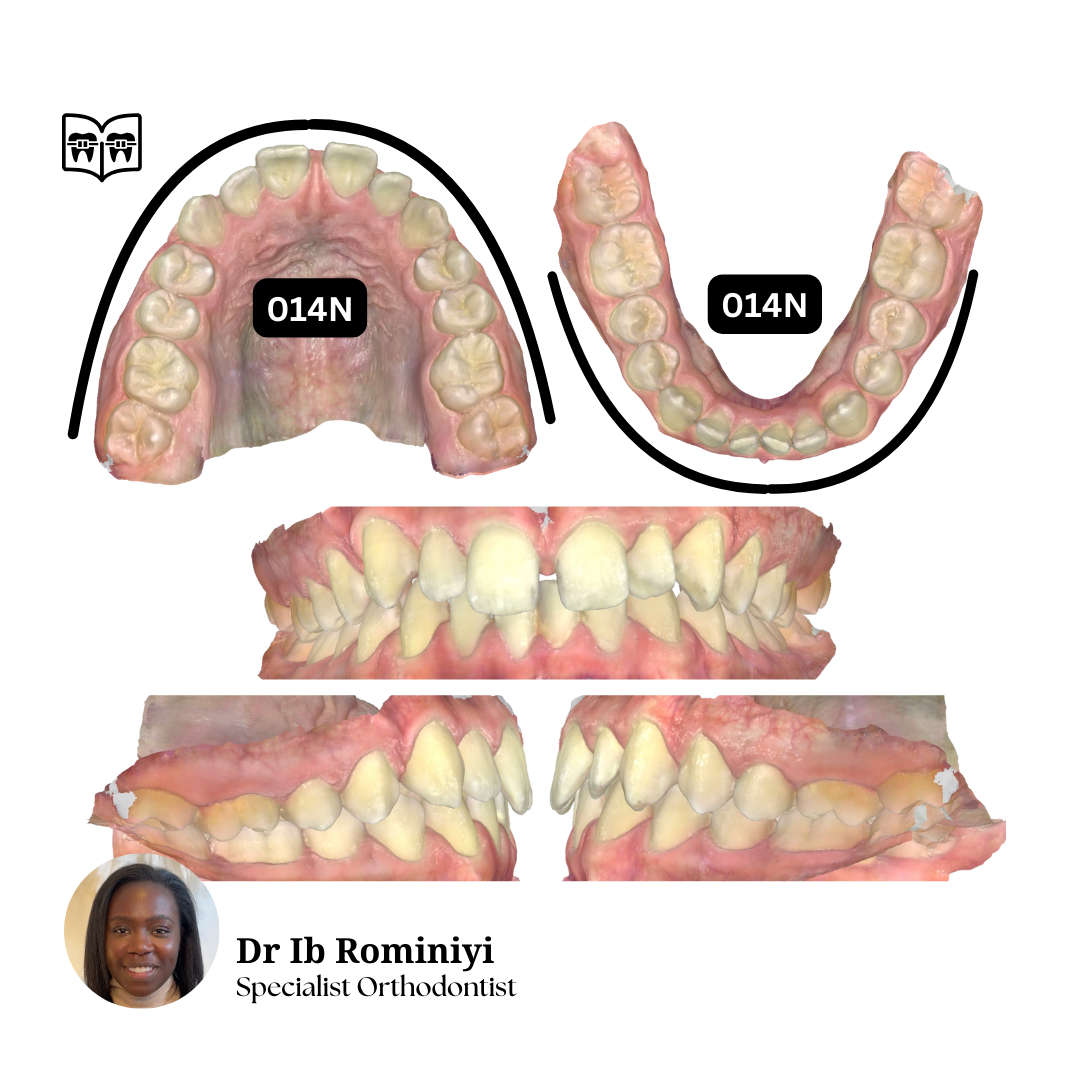

M E N T O R I N G M O M E N T

#1

Dentist's Question: I'm currently in upper 19x25N, lower 18x25S and the lateral open bites and centrelines are getting worse.

How would you improve the bite?

What mechanics & archwires would you use from here?